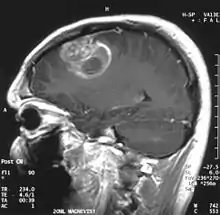

- اختبارات التصوير: وغالبًا ما يستخدم التصوير بالرنين المغناطيسي للمساعدة في تشخيص أورام الدماغ. في بعض الحالات، قد يتم حقن صبغة (مواد تباين) خلال وريد في ذراع المريض أثناء دراسة التصوير بالرنين المغناطيسي للمساعدة في إظهار الاختلافات في أنسجة الدماغ.

قد يساعد عدد من مكونات التصوير بالرنين المغناطيسي المتخصصة — بما في ذلك التصوير بالرنين المغناطيسي الوظيفي، وتصوير التروية بالرنين المغناطيسي وتنظير الطيف بالرنين المغناطيسي — في تقييم الطبيب للورم وخطة العلاج.